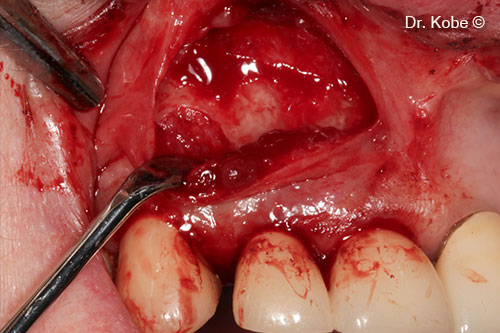

Access to the defect

Root surface cleaned